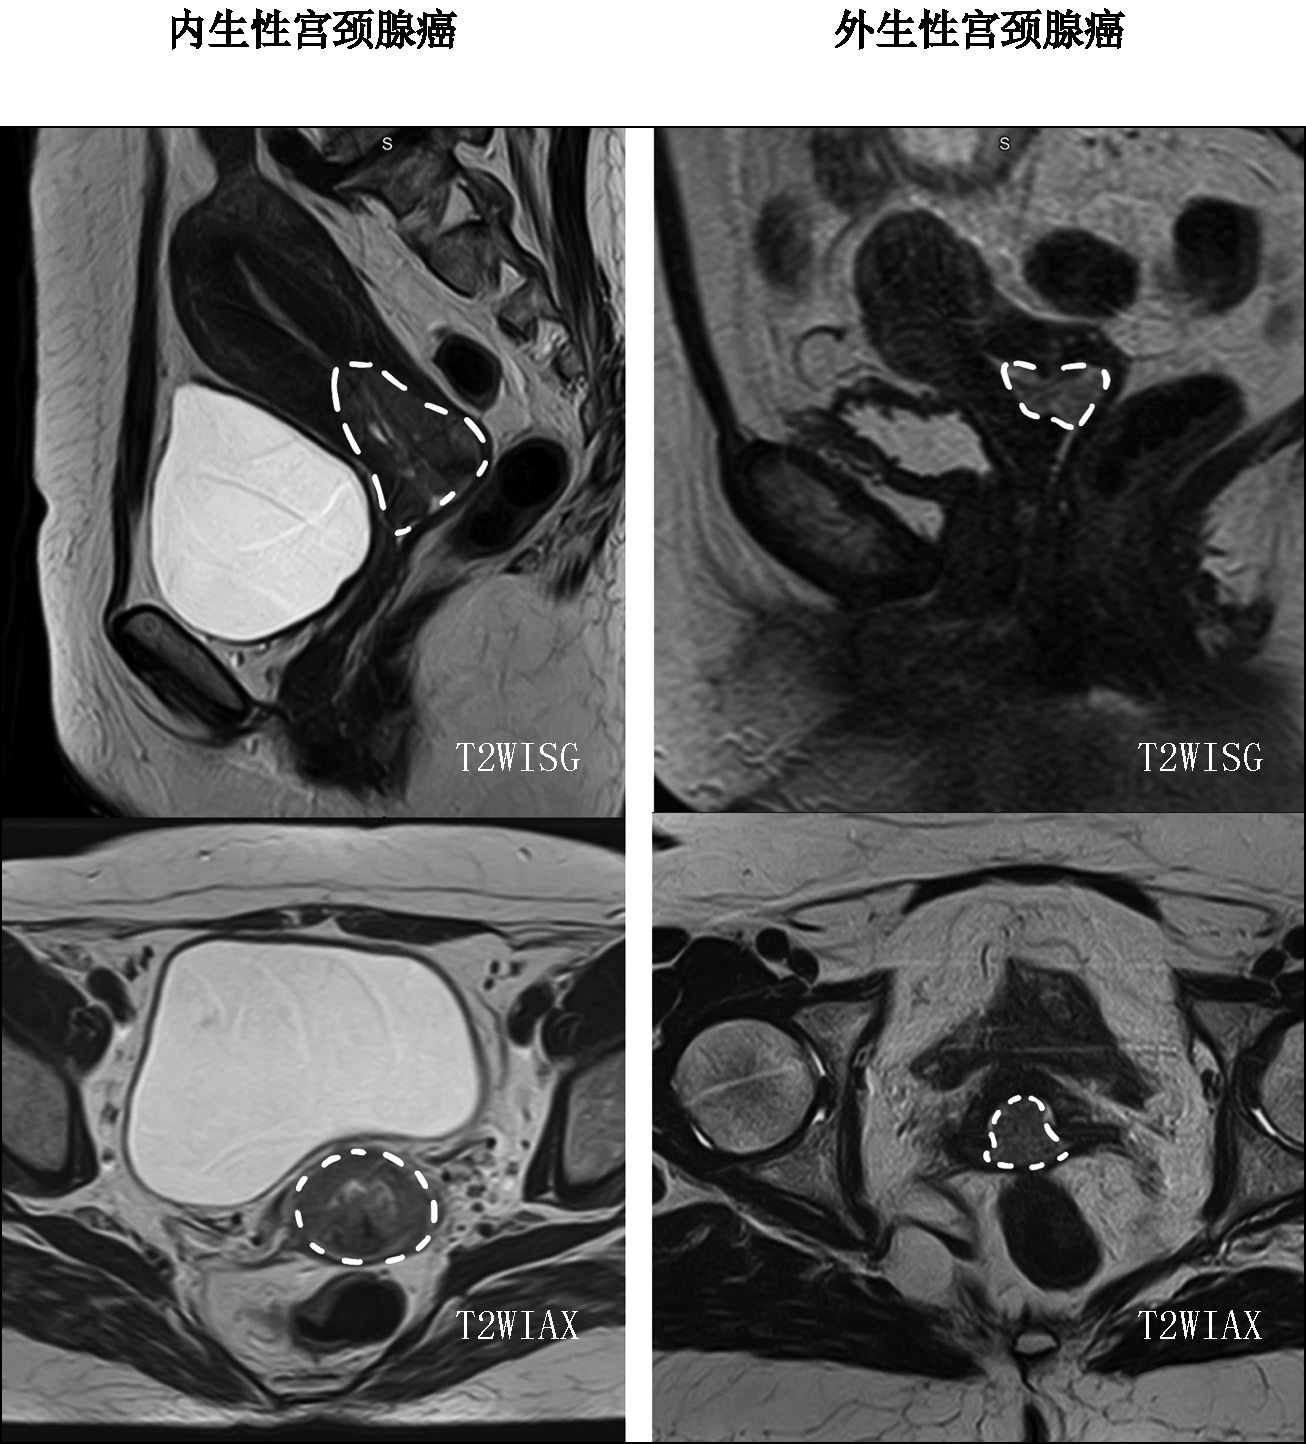

Differential diagnosis of the location of the primary tumor (whether the observed uterine abnormalities were endometrial carcinoma with cervical involvement or cervical carcinoma with endometrial involvement) was critical in the diagnostic search of gynecologists and radiologists for detecting uterine adenocarcinoma. All diagnostic controversies with predominant involvement in the uterine cavity were further reviewed by pathologists, and in all patients, endocervical adenocarcinoma (tumor of the cervix) was confirmed. Therefore, four types of tumor macrostructure were retrospectively classified based on the predominant location of the tumor according to MRI and pathology data (Fig. 4):

- Predominance of tumor in the cervix (n = 13; 65%)

- Predominance of tumor in the uterine body (n = 2; 10%)

- Equal involvement of endocervix and endometrium (n = 2; 10%)

- Isolated cervical lesion with CA lesion seeding into the uterine cavity (in the endometrium), confirmed by pathology and immunohistochemistry data (n = 3; 15%)

Fig. 4. Type of tumor macrostructure, T2-weighted images in sagittal plane, cervical adenocarcinoma.

Notably, type 2, 3, and 4 tumors were described as uterine body cancer on MRI, and only pathology examination confirmed primary CA.